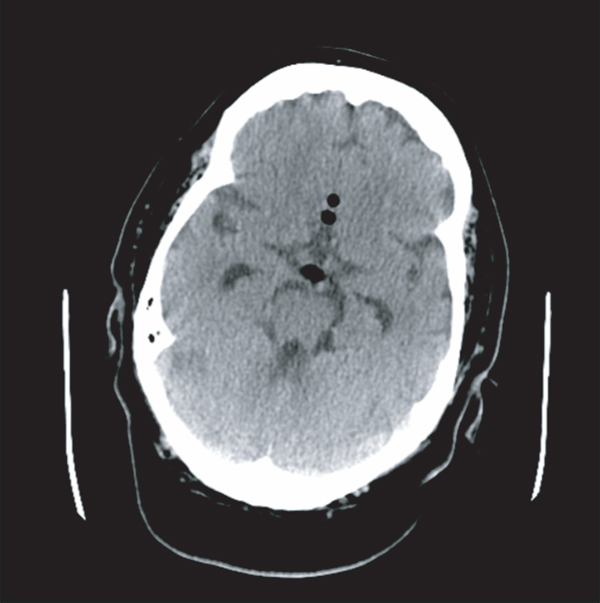

The patient demonstrated good progress during rehabilitation. Nasal CPAP was reintroduced (autoset with a range of 5-12 cm H2O) around five weeks postoperatively. Soon thereafter, she rapidly developed fever up to 39C, decreased level of consciousness, and nuchal rigidity, and was subsequently transferred back to our institution. Brain CT scan demonstrated hydrocephalus and pneumocephalus as shown in Figures 1 and 2. Sphenoidoscopy demonstrated left CSF fistula. A lumbar puncture revealed a cerebrospinal fluid with elevated leukocytes, glucose level of 6.8, and lactic acid of 6.8. Cultures did not demonstrate any pathogen. A diagnosis of culture-negative meningitis secondary to reopening of the surgical site by CPAP was postulated. The patient was treated with broad spectrum antibiotics, an external ventricular drain was installed, and the patient was monitored until her discharge.